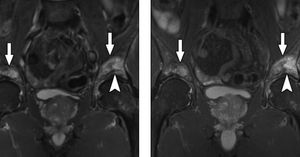

(left) Coronal STIR and (right) coronal T2W FSE Dixon (water image) of pelvis reveal high-signal edema within both acetabuli (arrows). There is associated linear area of low signal within right acetabulum (arrowhead), which suggests presence of insufficiency fracture. Improved SNR ratio and higher resolution of Dixon image allow better visualization of trabecular detail. Both techniques provide robust fat suppression. (Gerdes et al. 2007)